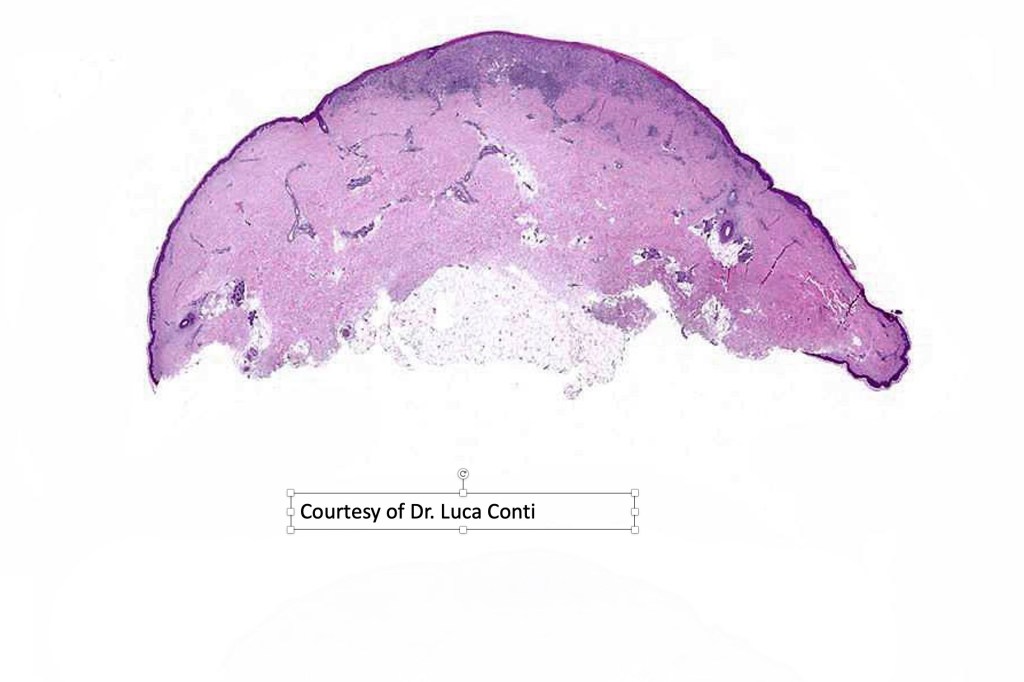

Histological features

•>5-10 mm

•Involve deep dermis or subcutis

•Asymmetrical, poorly circumscribed

•May show effacement/consumption of epidermis or ulceration

•Peripheral Pagetoid spread

•Large nodules which often show impaired maturation

•Loss of gradient with HMB45 and Ki67

•>20% Ki67 expression

•TERT promoter & PTEN mutations

•DNA copy-number variations